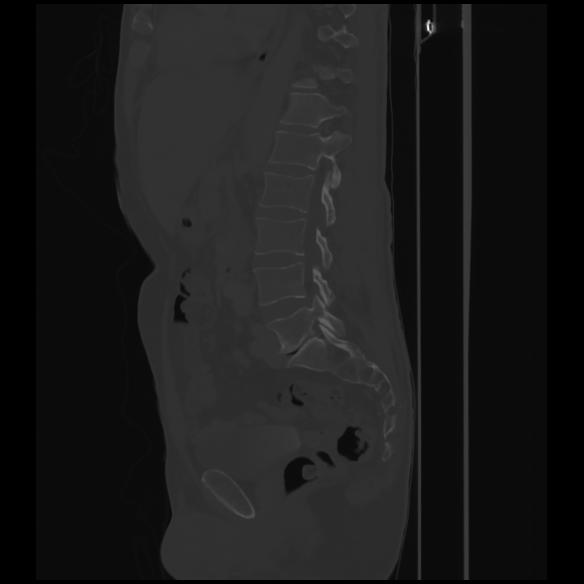

7 CUERPO,CE,Sagittal,3.000,CUERPO,Sagittal,